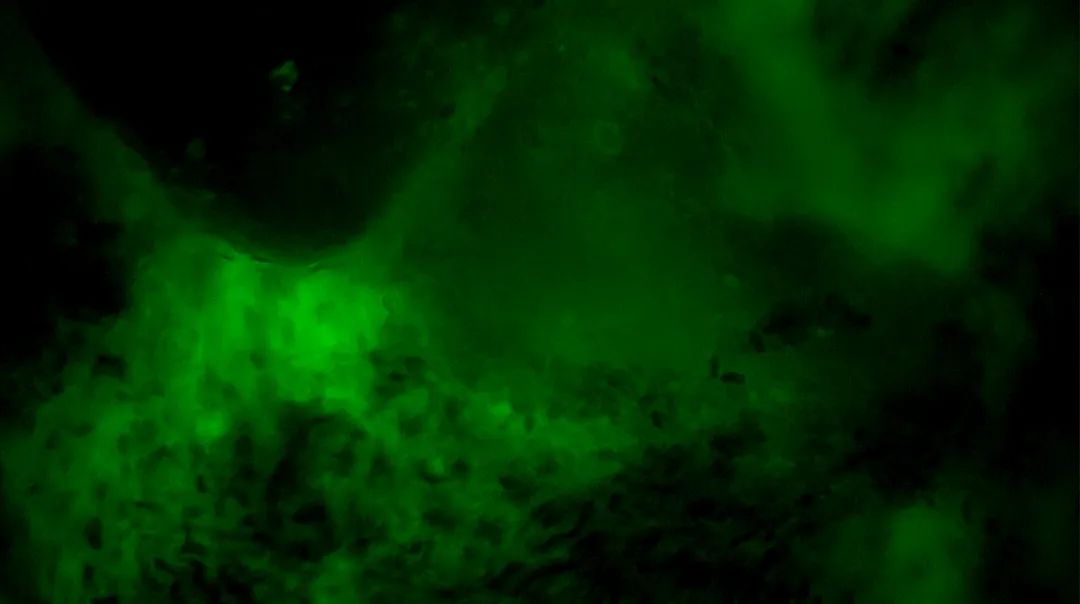

2

陽(yáng)性,細(xì)胞核異型、密集、分布不均勻